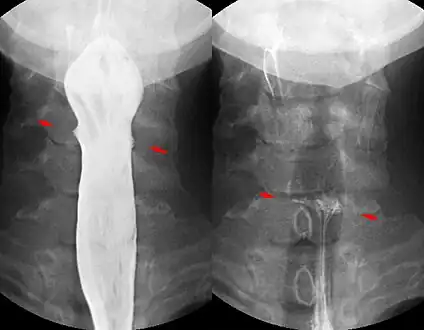

Fish bone pierced in the upper esophagus. Right image without contrast medium, left image during swallowing with contrast medium.

To obtain an image with any type of image detector the part of the patient to be X-rayed is placed between the X-ray source and the image receptor to produce a shadow of the internal structure of that particular part of the body. X-rays are partially blocked ("attenuated") by dense tissues such as bone, and pass more easily through soft tissues. Areas where the X-rays strike darken when developed, causing bones to appear lighter than the surrounding soft tissue.

Contrast compounds containing barium or iodine, which are radiopaque, can be ingested in the gastrointestinal tract (barium) or injected in the artery or veins to highlight these vessels. The contrast compounds have high atomic numbered elements in them that (like bone) essentially block the X-rays and hence the once hollow organ or vessel can be more readily seen. In the pursuit of nontoxic contrast materials, many types of high atomic number elements were evaluated. Some elements chosen proved to be harmful – for example, thorium was once used as a contrast medium (Thorotrast) – which turned out to be toxic, causing a very high incidence of cancer decades after use. Modern contrast material has improved and, while there is no way to determine who may have a sensitivity to the contrast, the incidence of serious allergic reactions is low.[1]